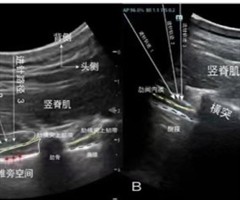

超声引导下横突间阻滞的临床应用进展

摘要:超声引导下横突间阻滞(Intertransverse processblock,ITPB)是一种类椎旁神经阻滞技术,其核心操作是在超声实时引导下,将局麻药注射至肋横突上韧带后方的横突间组织复合体内。因其操作简单,安全有效,并发症少而受...